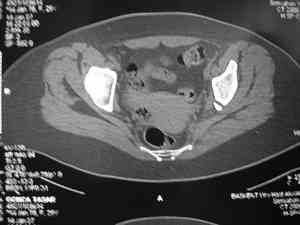

Dear group,30 years age female MVA front seat, head trauma + post column left acetabular fracture, 2.5 weeks skeletal traction. She is now conscious but still confused without any surgical treatment for brain edema.

Latest X rays and CAT is attached.Fracture within first 1.5 cm from the weight bearing dome, although AP and Obtrator oblique good, iliac oblique view reveals some displacement.I'm not sure that nonsurgical treatment will be OKHüseyin DemirorsBaskent UniversityDept of Orthopedics and TravmatologyAnkara TURKEY

My vote, given the amount of displacement on the iliac oblique and CT scan, would be for ORIF thru a posterior approach ASAP - these get pretty tough

I may get beat up for this, but I see very little displacement that concerns me on the CT. The radiograph is more concerning. I suspect it could look better, and the gap made smaller on CT. Not sure if it will affect outcome. I might give it a shot and try to see what could be done.